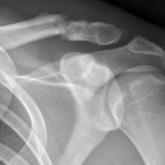

The Diagnosis and Initial Treatment of Patellofemoral Disorders

Our purpose is to provide simple guidelines for the diagnosis and early care of patellofemoral disorders. Any clinician who treats knee problems,...